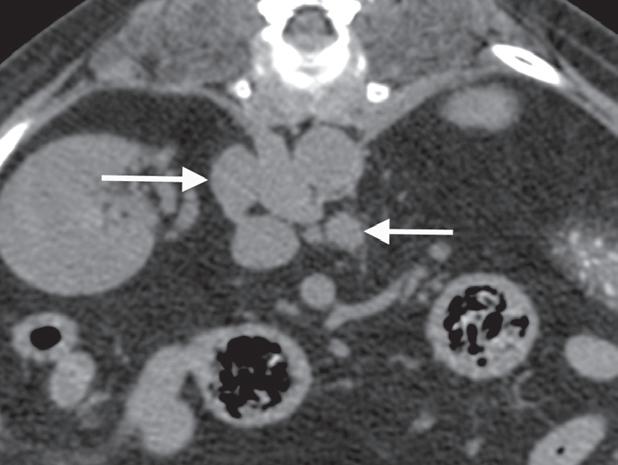

Rycina 5.6.6. Przysadkowozależna nadczynność kory nadnerczy (pies) TK

Badanie wykonano u 12-letniego, kastrowanego boston teriera z podejrzeniem przysadkowozależnej nadczynności kory nadnerczy. W badaniu natywnym oba nadnercza (a, b – strzałki) są powiększone i zaokrąglone, a także wykazują jednorodną densyjność tkanek miękkich. Widoczna jest mineralizacja ściany tętnicy krezkowej przedniej, która jest zmianą wtórną do zespołu Cushinga (b – gwiazdka). Obraz po podaniu dożylnego środka kontrastowego mózgowia ujawnia duży, intensywnie wzmacniający się rozrost przysadki (d – otwarta strzałka), przypuszczalnie o charakterze funkcjonalnym